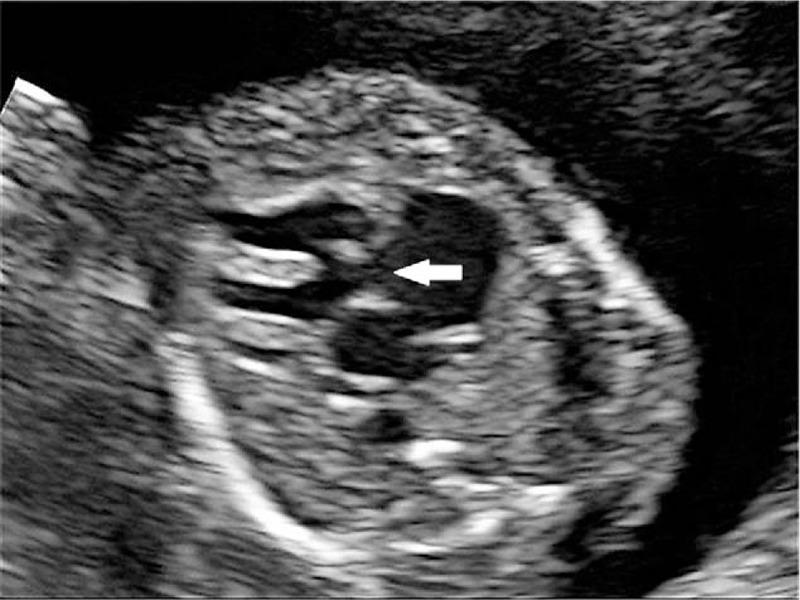

The prenatal phenotype of case 1 included sonographic markers such as enlarged nuchal translucency (NT), absent nasal bone, short femur and humerus length, and several structural malformations involving Dandy-Walker malformation and congenital heart defects. The prenatal phenotype of Case 2 are sonographic markers, including enlarged NT, thickened nuchal fold, ascites, and polyhydramnios without apparent structural malformations.

Conventional G-band karyotype appears normal in case 1, while it shows normal chromosomes with a small supernumerary marker chromosome (sSMC) in case 2. Genetic etiology was left unknown until single-nucleotide polymorphism-based array (SNP-array) was performed, and segmental paternal UPD 22 was identified in case 1 and segmental paternal UPD 14 was found in case 2.